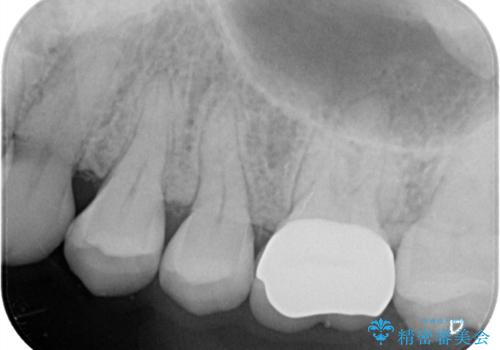

きれいな被せ物になり、患者さんにも満足していただけました。

歯牙の破折を防ぐために、セラミッククラウンにて修復しています。